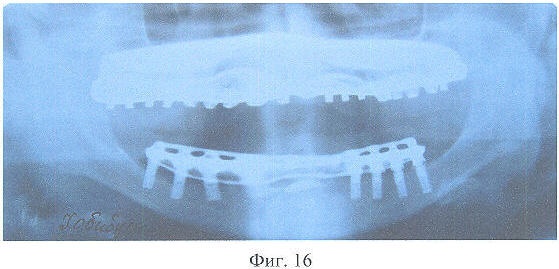

На фиг.16 – рентгенограмма больной X. через 3 года после зубного протезирования.

Динамическое наблюдение показало, что адаптация к протезам протекала в течение 14-и суток, после чего больная отмечала удовлетворительное функциональное состояние зубочелюстного аппарата. При осмотре через 3 года больная жалоб не предъявляла, состояние протезов удовлетворительное. Рентгенологически признаков резорбции костной ткани вокруг дентальных имплантатов не выявлено.